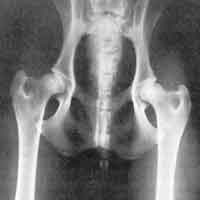

HD (Hüftgelenksdysplasie)

HD ist eine Fehlbildung der Hüftgelenke - das heißt Oberschenkelkopf und Gelenkpfanne passen nicht korrekt aufeinander. Diese Fehlbildung kann unterschiedlich ausgeprägt sein und tritt oft beidseitig auf.

Wir unterscheiden zwischen 5 verschiedenen Schweregraden der HD.

HD-frei - A

Das Gelenk ist absolut unauffällig und der Norbergwinkel beträgt 105 Grad oder mehr

HD-Verdacht/Grenzfall - B

Der Norbergwinkel beträgt 105 Grad oder mehr und die Gelenkpfanne und/oder der Schenkelkopf sind leicht ungleichmäßig oder aber Gelenkpfanne und/oder Schenkelkopf sind gleichmäßig, aber der Norbergwinkel beträgt weniger als 105 Grad

leichte HD -C

Norbergwinkel 100 Grad oder kleiner, ungleichmäßiger Oberschenkelkopf und Gelenkpfanne. Unter Umständen sind auch schon leichter arthrotischer Veränderungen zu bemerken.

mittlere HD - D

Norbergwinkel größer als 90 Grad und deutliche Ungleichmäßigkeiten von Oberschenkelkopf und Gelenkpfanne. Veränderungen des Pfannenrandes und/oder arthrotische Veränderungen sind zu erwarten oder schon vorhanden.

schwere HD - E

Norbergwinkel weniger ald 90 Grad, abgeflachter Pfannenrand, auffällige Veränderungen an Oberschenkelkopf und Gelenkpfanne. Deutliche arthrotische Veränderungen sind zu erwarten oder schon vorhanden.